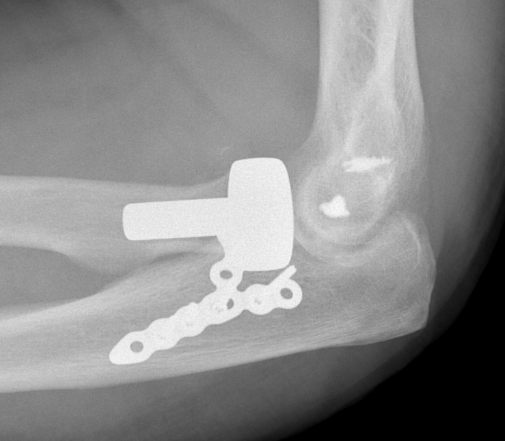

Terrible Triad

Definition

Elbow dislocation with radial head fracture + coronoid fracture + MCL tear

Technique

Surgical Algorithm

Principles

1. Restore coronoid stability - ORIF type II / III, suture repair type I

2. Restore radial head stability - radial head ORIF or arthroplasty

3. Restore lateral stability - LCL repair and common extensor origin +/- reconstruct +/- internal brace

4. +/- Restore medial stability - repair MCL if residual stability

5. +/- External fixation / internal joint fixation

| Type II / Reconstructable radial head | Type III / Radial head arthroplasty |

|---|---|

|

Lateral / Kocher approach - ORIF radial head with screws/ plate - LCL +/- common extensor origin repair - reassess stability |

Lateral / Kocher / Kaplan / EDC split approach - excise radial head - can suture small coronoid process fracture through gap - radial head replacement - LCL +/- common extensor origin repair - reassess stability

|

|

Unstable - medial approach - FCU split / over the top approach to coronoid process - ORIF coronoid process with sutures / buttress plate / screws - MCL repair +/- common flexor origin repair - reassess stability |

Unstable - medial approach - FCU split / over the top approach to coronoid process - ORIF coronoid process with sutures / buttress plate / screws - MCL repair +/- common flexor origin repair - reassess stability |

| Unstable - external fixation | Unstable - external fixation |

Radial head replacement with lag screw fixation of Type II coronoid

Radial head replacement with lasso fixation of small coronoid fragment